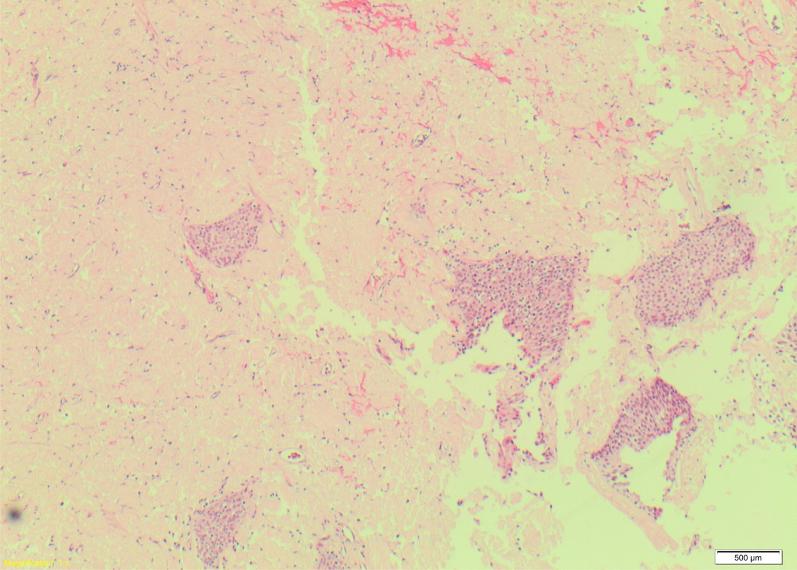

Primary and localized amyloidosis of the urinary tract is considered to be a rare clinical entity with approximately 160 cases documented in the literature. Here we present a case of a 77 year old gentleman with painless visible hematuria. Flexible cystoscopy revealed abnormal and polypoidal bladder mucosa. Transurethral resection of these lesions revealed histology with congo-red staining and positive green-apple birefringence, these findings are consistent with amyloidosis. There has so far been no sign of recurrence in this gentleman, with routine cystoscopic surveillance. Here we present a literature review on the presentation, diagnosis and management of this rare condition.

原发性局限性泌尿道淀粉样变性被认为是一种罕见的临床病症,文献记载约有160例病例。在此,我们报告一例77岁男性患者,其有无痛性肉眼血尿。软性膀胱镜检查发现膀胱黏膜异常且呈息肉样。经尿道切除这些病变组织后,刚果红染色及阳性苹果绿双折射的组织学检查结果显示,这些发现符合淀粉样变性。到目前为止,该患者在常规膀胱镜监测下尚无复发迹象。在此,我们对这种罕见病症的临床表现、诊断及治疗进行文献综述。